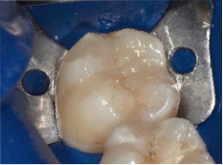

Carie interdentale su premolare superiore: viene trattata con approccio non convenzionale (mini-invasivo laterale, reso possibile dall'uso di sistemi ingrandenti).

Piccola carie interdentale su molare con vecchia otturazione. Vengono rimossi la carie e la vecchia otturazione e si esegue una otturazione in resina composita.